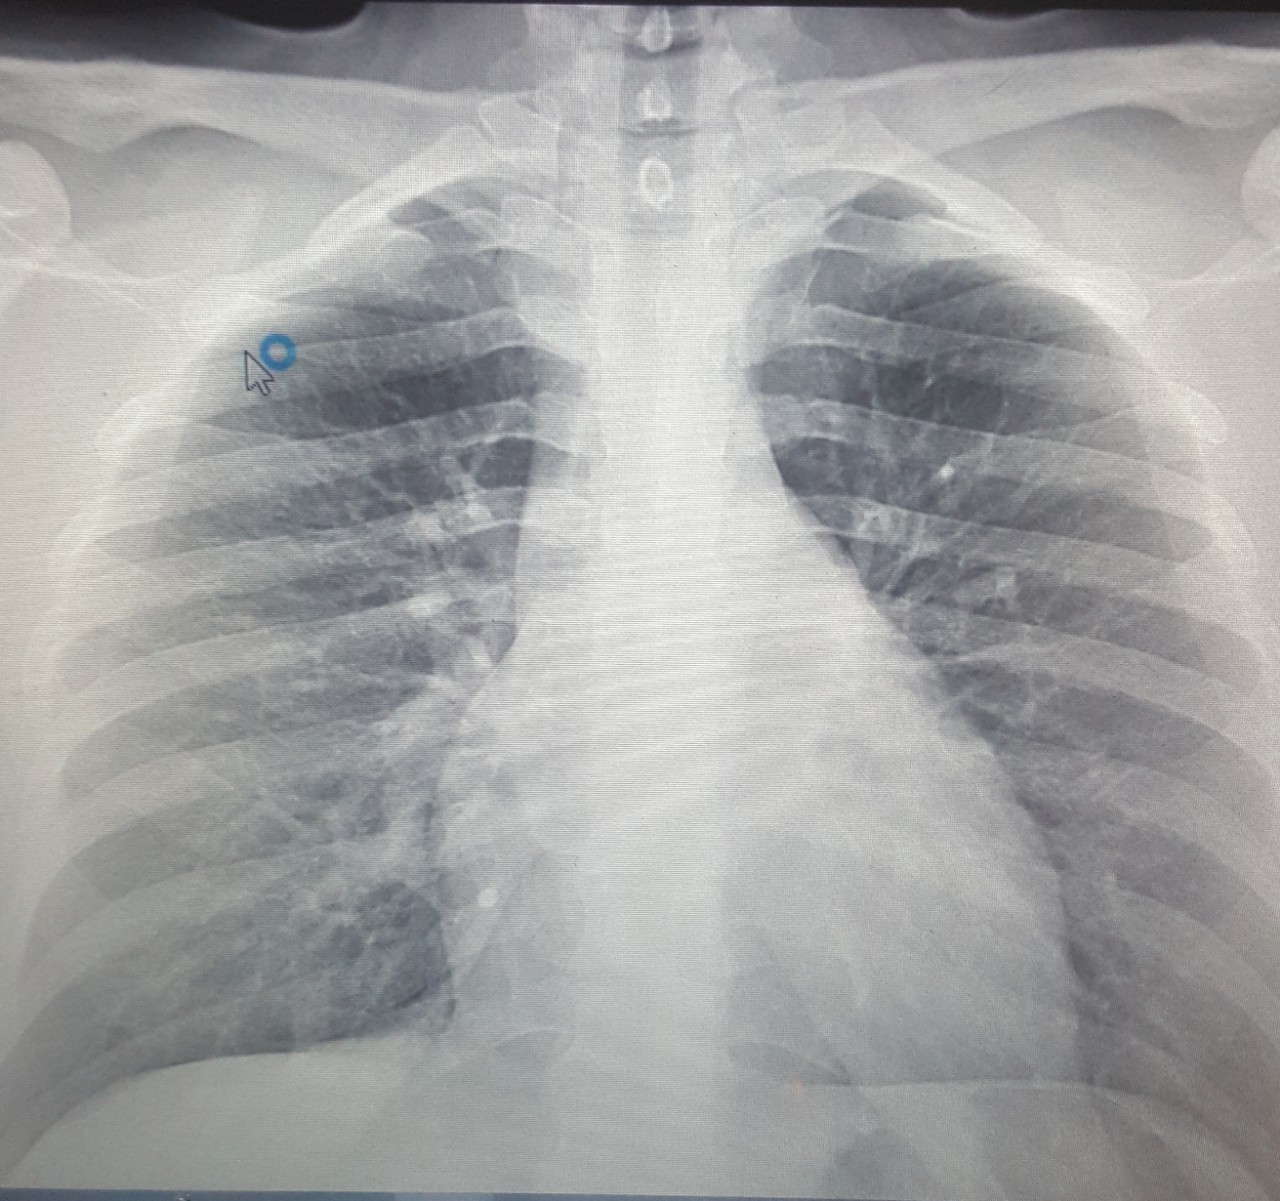

Что такое малоконтрастная рентгенограмма органов грудной клетки